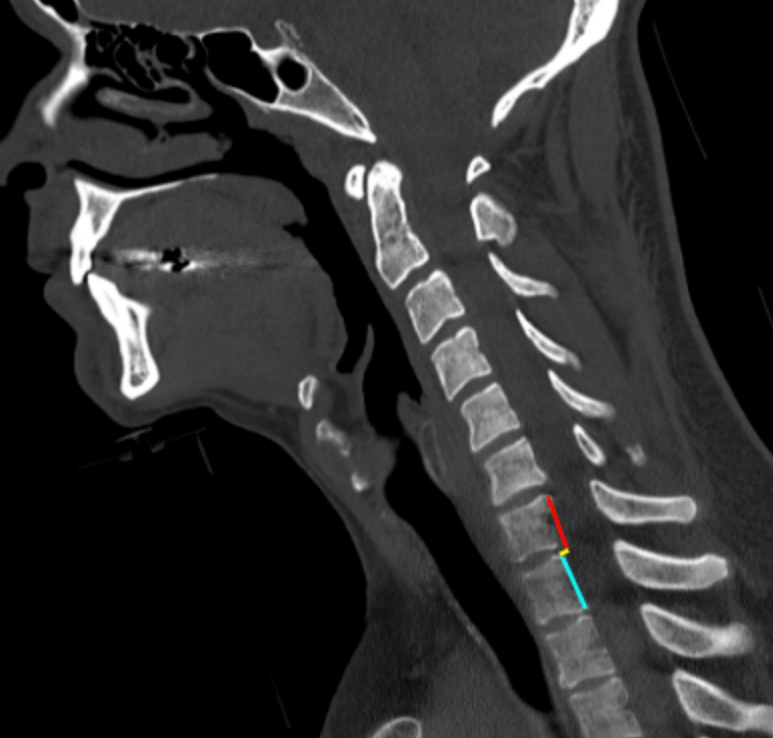

Image Type Cervical Spine X-Ray CT Scan MRI Scan Atlantodental Interval (ADI) Basion–Axial Interval (BAI) Basion–Dens Interval (BDI) Canal Occupying Ratio (COR) Clivo-Axial Angle Facet Joint Overlap (Percent Overlap Method) Facet Joint Step-Off/Dislocation Grabb-Oakes Measurement (pB - C2 line) Occipital Condyle–C1 Interval (CCI) Posterior Atlantodental Interval (PADI) Power’s Ratio Sagittal Vertical Axis (SVA) Segmental Angle Translation on Sagittal Reconstruction